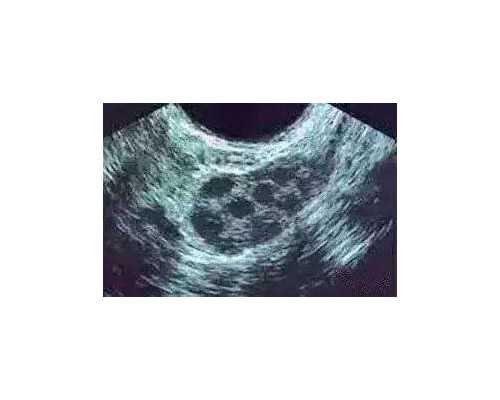

精子与卵子送到实验室内后,就会在实验员的操作下进行体外授精,并培养成早期胚胎,等待移植回母体内。

胚胎,,不同的是医生是将胚胎经过移植导管送入到女方子宫腔内,使胚胎能够在子宫腔内顺利着床并持续成长发育。移植后,医生会根据患者的情况制定黄体支持方案,有口服、针剂、阴道栓剂等多种形式。14天后回院验孕,如果成功,黄体支持需要坚持三个月左右。